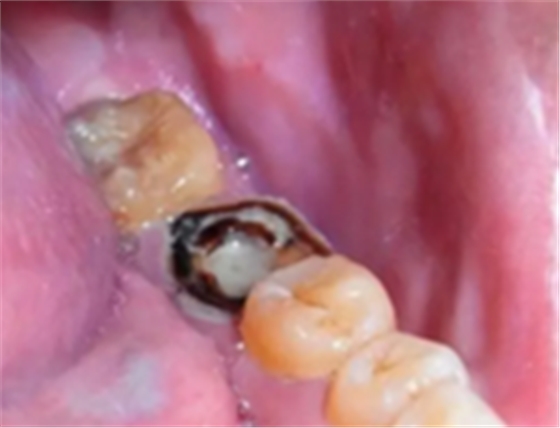

嚴(yán)重蛀牙:牙冠遭到嚴(yán)重破壞的,而且牙根或牙周情況無(wú)法做樁冠修復(fù)的。

為什么有些牙齒不能拔?拔牙無(wú)小事!